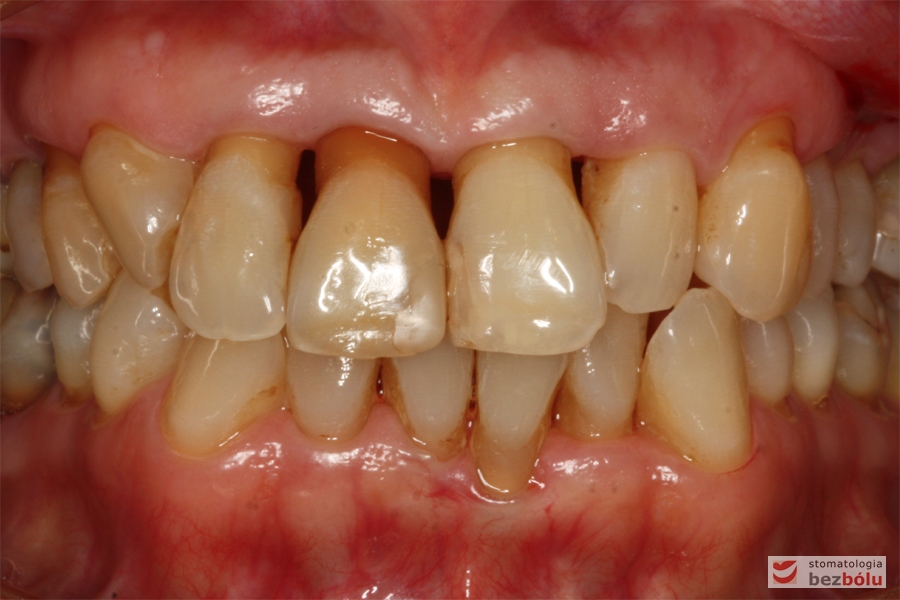

Zęby w zwarciu - widok frontalny, zgryz krzyżowy w pozycji kłów, paradontalny status siekaczy

Zęby w zwarciu – widok frontalny, zgryz krzyżowy w pozycji kłów, paradontalny status siekaczy